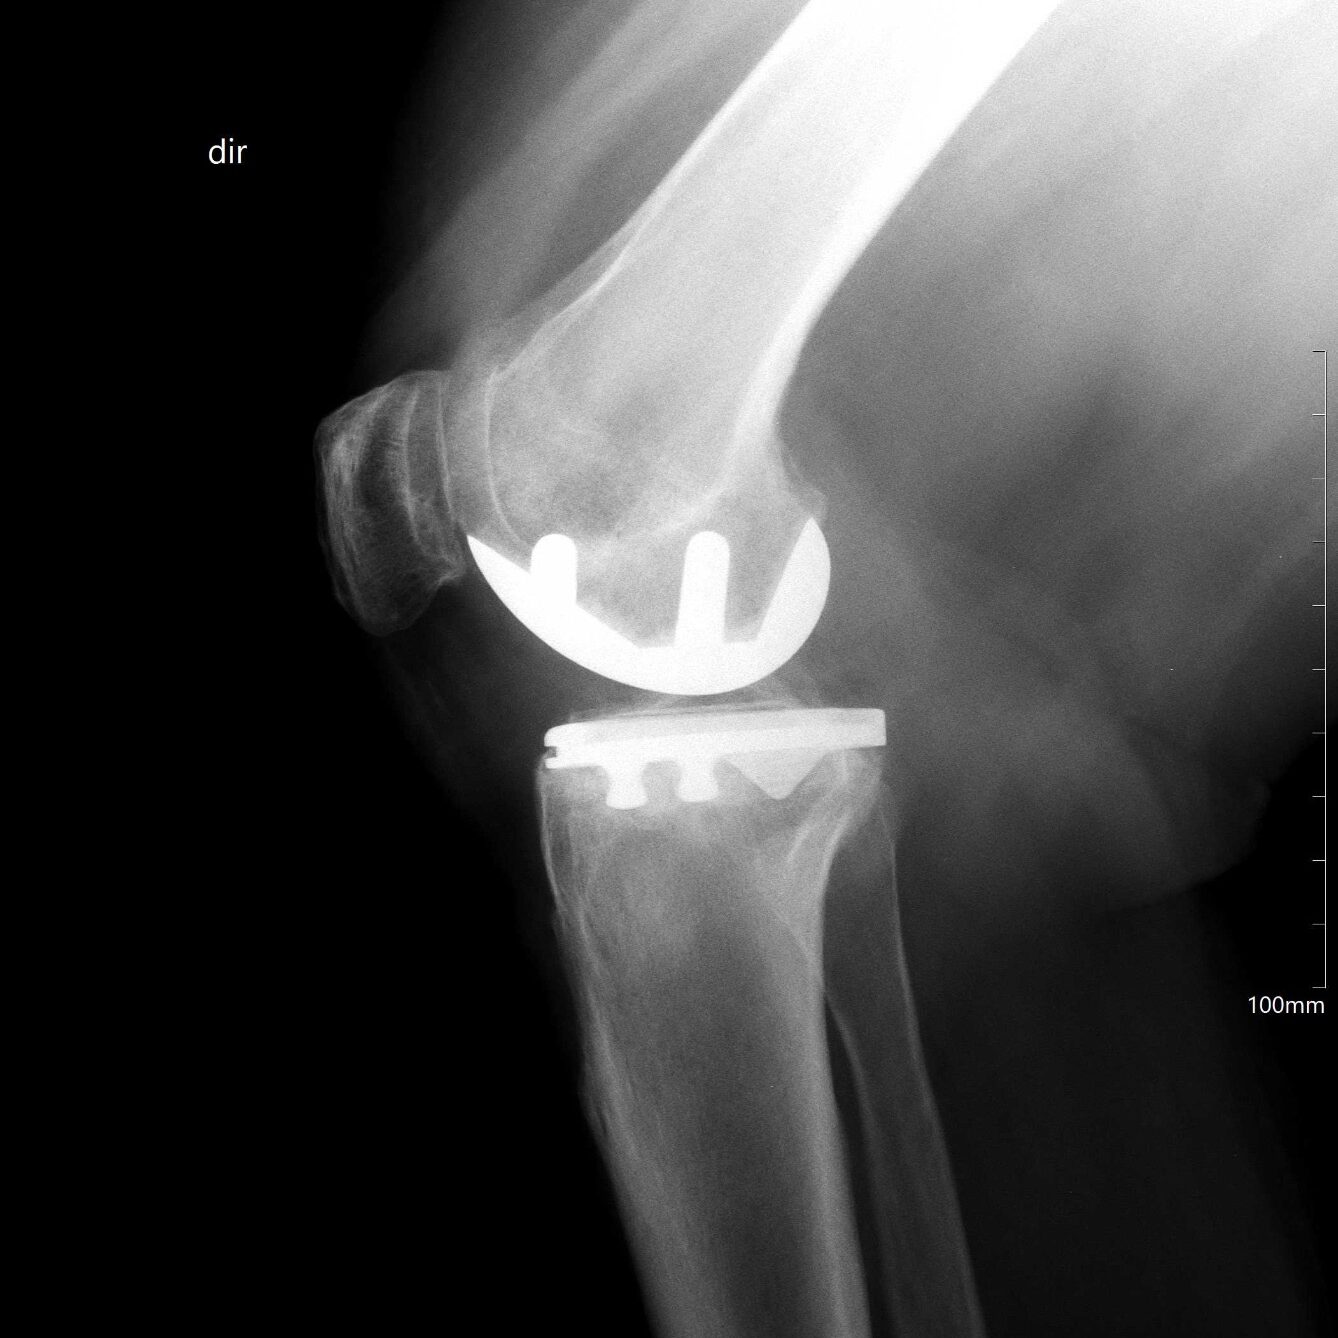

A artroplastia é a cirurgia onde se substitui a articulação acometida pela artrose grave por uma prótese, ou seja, uma “junta artificial”.

Apesar de ser uma cirurgia de alta complexidade, apresenta alto índice de bons resultados com durabilidade média de 10 a 20 anos, segundo a literatura mundial.

A artroplastia pode ser total, quando toda a articulação é substituída, ou parcial, quando parte dela recebe a prótese. No caso do joelho, a artroplastia parcial é chamada de unicompartimental, pois apenas um compartimento está degenerado e é substituído.

Existem diferentes tipos de próteses e cada uma delas tem suas indicações específicas baseadas no grau da doença, instabilidade, defeito ósseo, deformidade, rigidez articular, entre outras. É fundamental a avaliação por um especialista para o planejamento adequado!